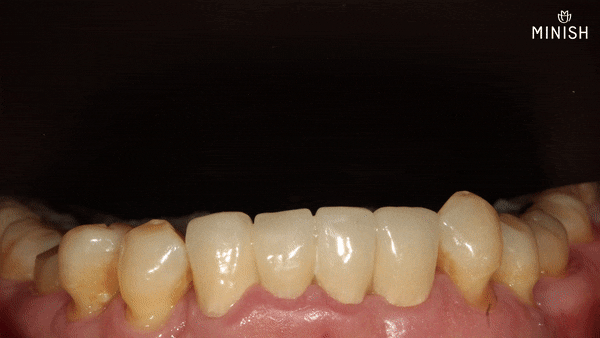

말 못할 고민은 치아에서도 시작됐습니다. 평택엄마의 아랫니는 틀어지고 벌어져 있었고, 보기에도 예쁘지 않았을 뿐더러 틈 사이로 음식물이 자주 끼고, 말을 할 때 침이 새는 불편함도 뒤따랐습니다. 늘어나는 불편함에 결국 부담을 무릅쓰고 크라운 브릿지를 선택하게 된 것도 그런 이유에서였습니다.

겉으로는 가지런해 보이는 아랫니,

하지만 그 속 사정은 달랐습니다.